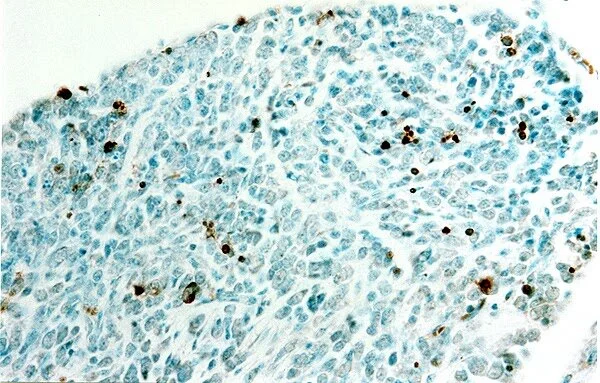

EmbeddedImage (6).jpg

TUNEL-labeled section counterstained with methyl green. This 10 µm paraffin section was cut from a dorsal root ganglion of a mouse embryo (E17). The section was processed for detecting neuronal apoptosis (brown) with FD NeuroApop™ Kit (cf. Products, Cat. #NDT205) and then counterstained with methyl green.